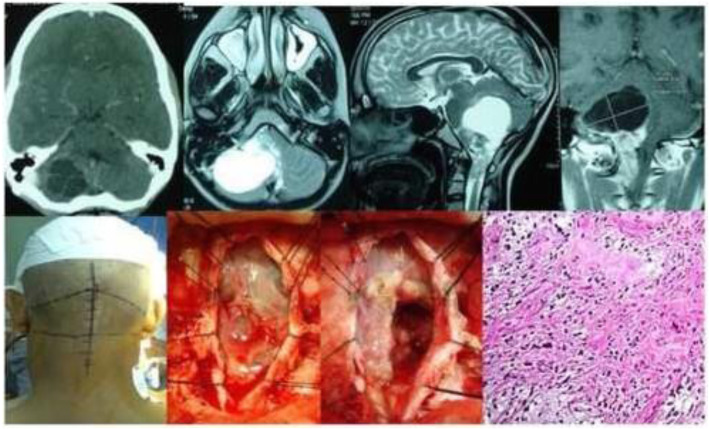

Fig. 1.

CT scan and MR images of Medulloblastoma in a 12-year-old male child showing intra-operative images in sitting position. Microphotograph (H&E; × 200)